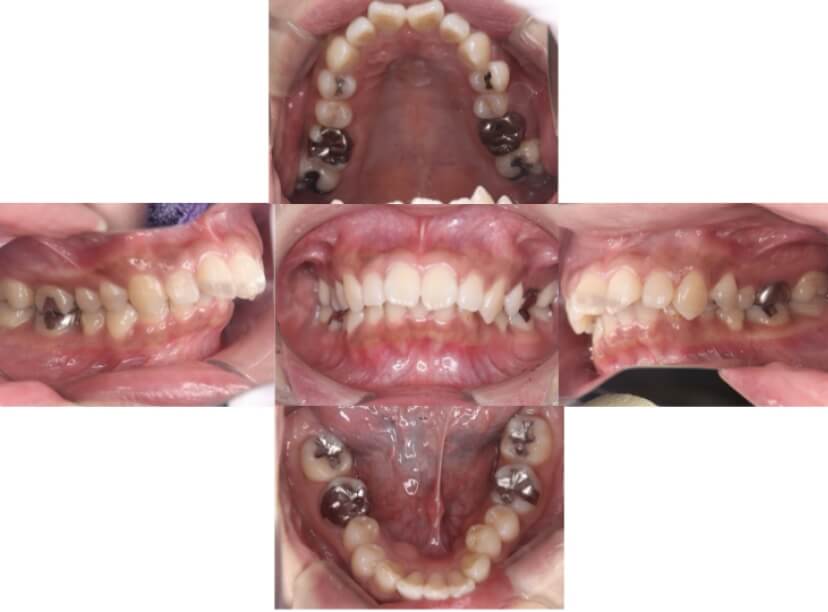

症例2

上下顎前突、叢生

抜歯

ブラケット矯正

上下顎前突、叢生(上下出っ歯、上下の前歯のガタガタ)のケースです。

装置はラビアル(上下表側)で、上下顎の小臼歯を4本抜歯を行っています。抜歯したスペースを使って、上下の前歯の後方移動と叢生(ガタガタ)の改善を行っています。

主訴 前歯のガタガタと口元がでているのが気になる。

年齢・性別 30歳 女性

お住まいの地域 東京都大田区

治療方針 抜歯スペースを利用して上前歯の叢生(ガタガタ)と口元突出の改善

抜歯部位 上下顎左右第一小臼歯

使用装置 ラビアル(上下表側)、顎間ゴム

治療期間 1年11か月

治療回数 13回

リテーナー クリアリテーナー

BEFORE

AFTER